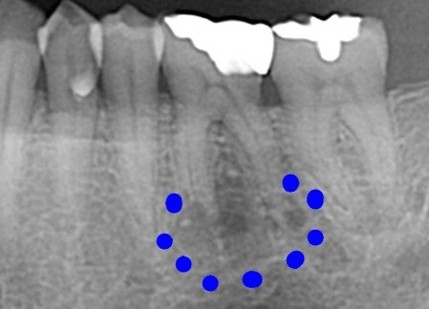

治療後 ![]() |

詰め物を外し、壊死した神経を取り除き根っこを傷めないように丁寧に根管治療を行いました。 |

現在は痛みも腫れもなく、経過良好です。 |